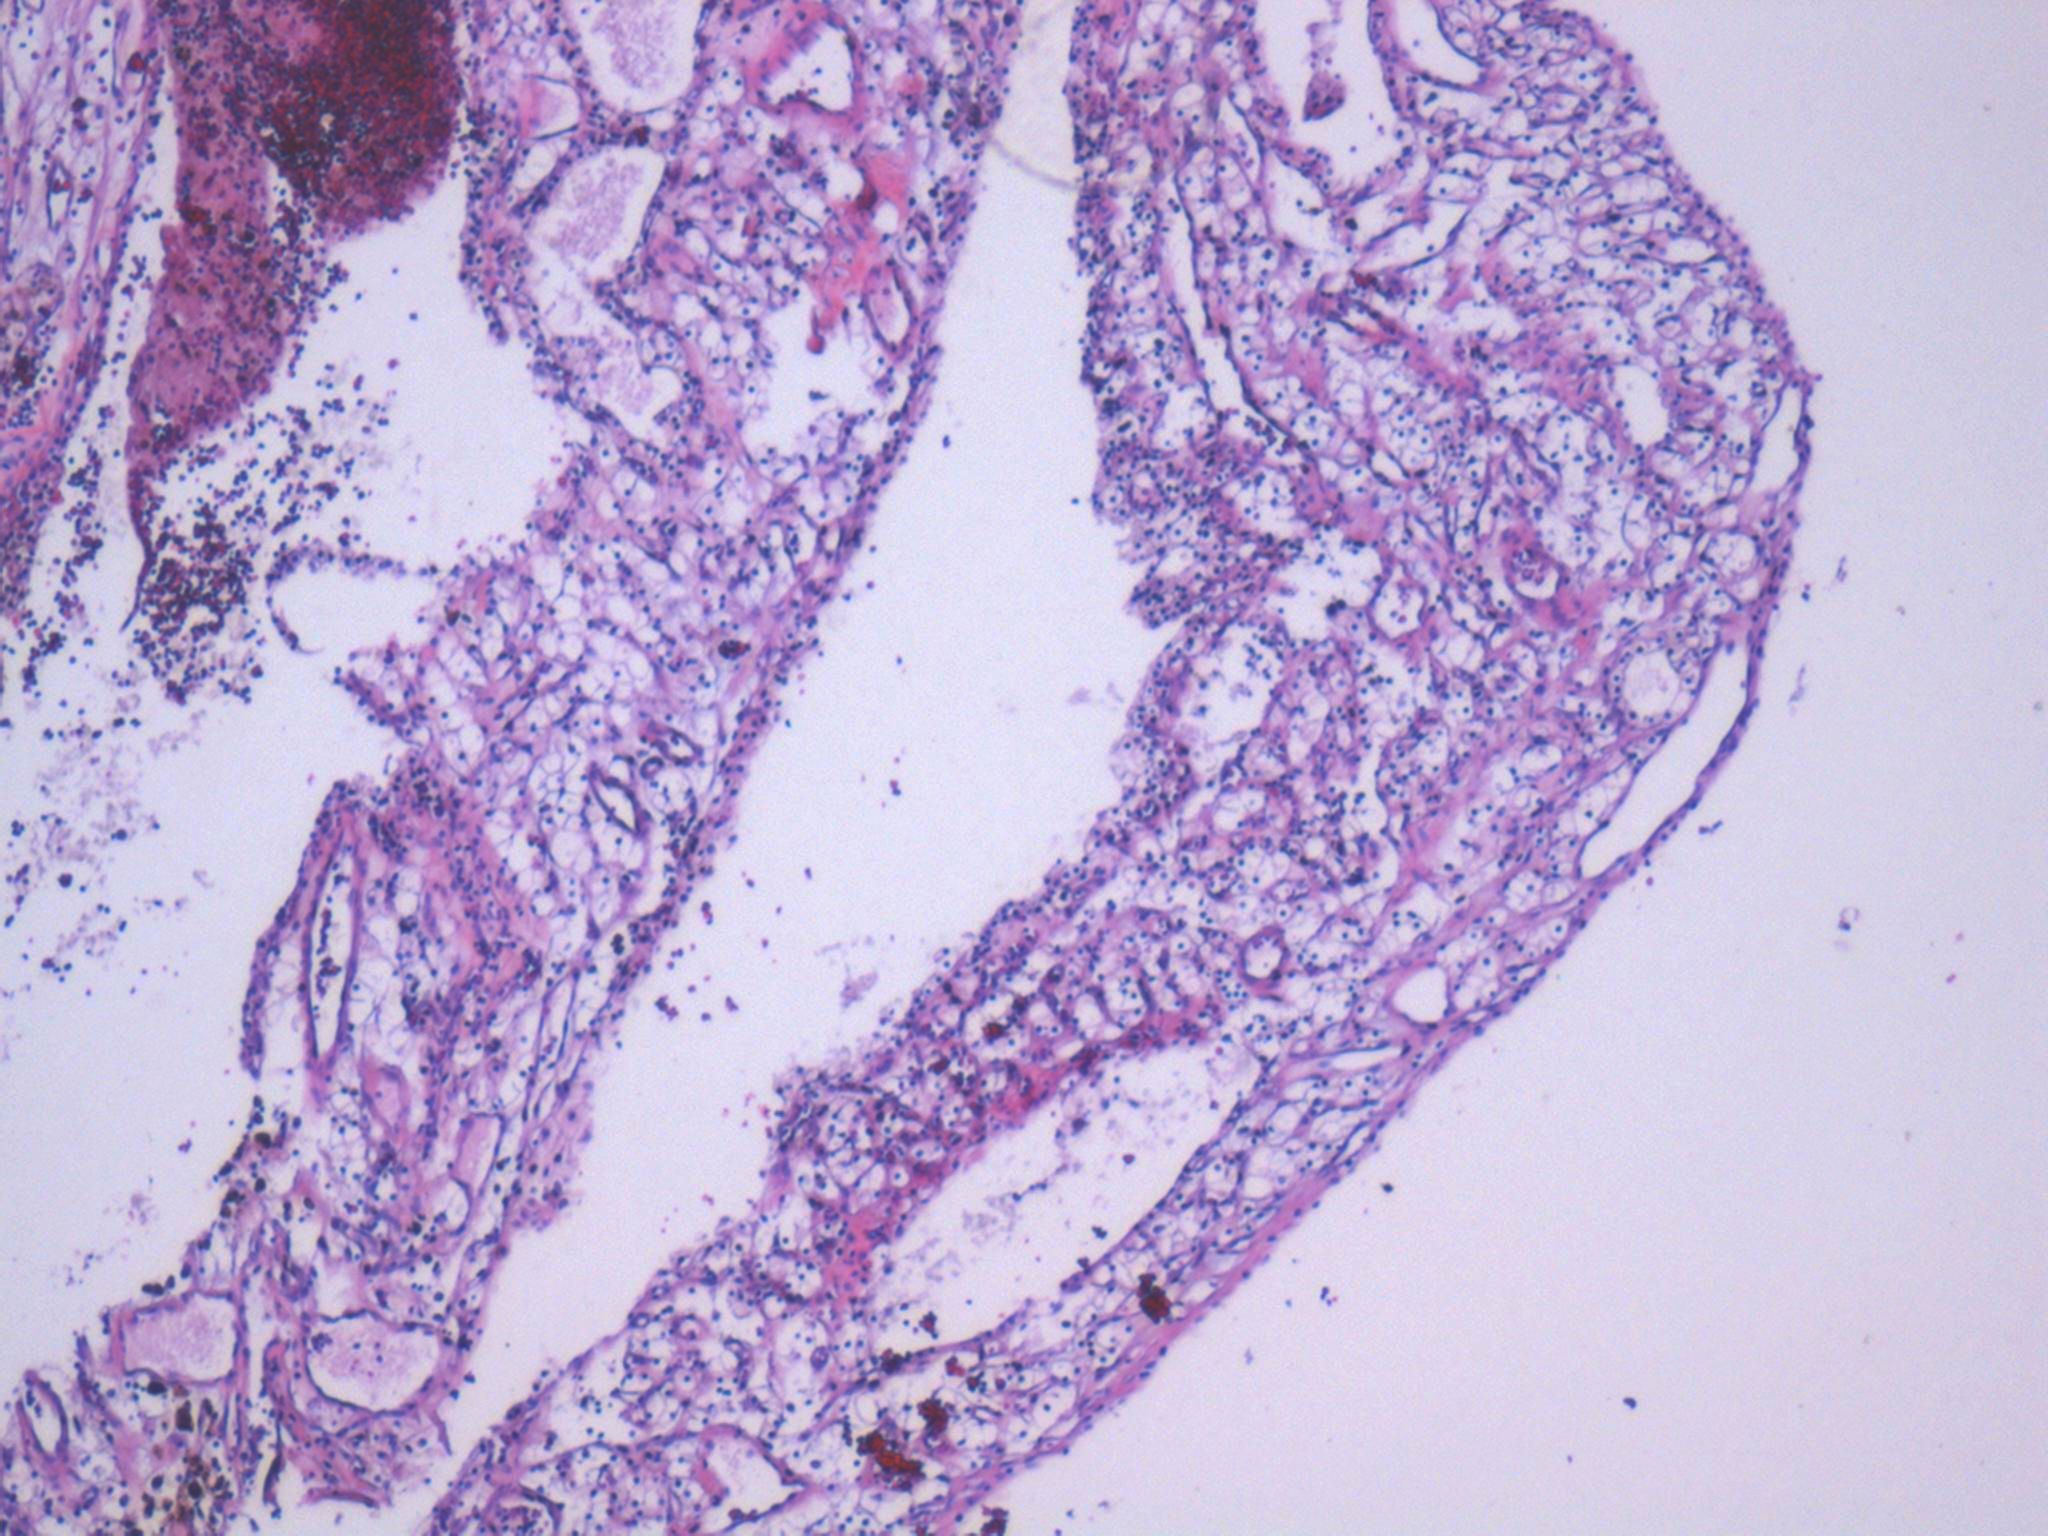

Consensus grade: Clear cell RCC

clear cell RCC with cystic changes

Cystic tumour with clear cells.